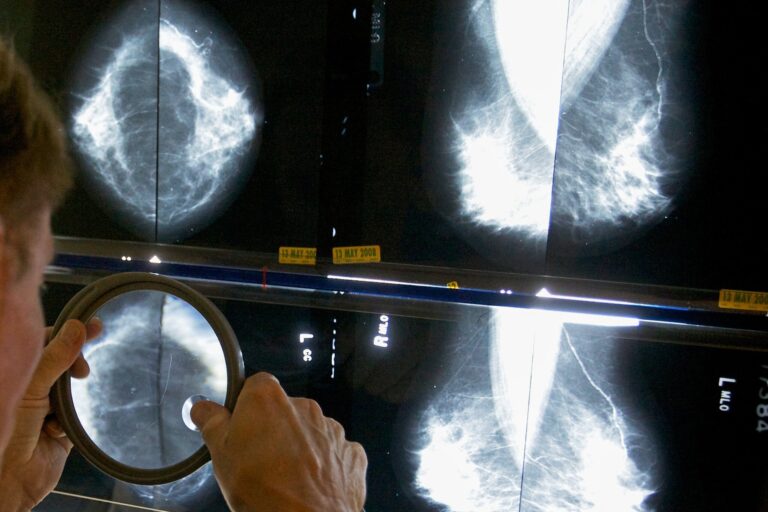

COVID-19 forced many people to postpone cancer screenings — colonoscopies, mammograms and lung scans — as the coronavirus overwhelmed doctors and hospitals, especially in 2020.